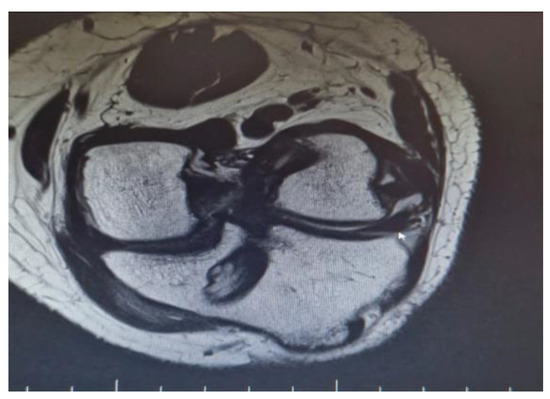

There were also a couple of cases on which a single Achilles allograft was used to reconstruct both the ACL and MCL or the ACL and LCL and ALL. In the cases where the ACL and MCL were reconstructed, the ACL was reconstructed in a standard manner, with the Achilles bone block on the femoral condyle, and after fixing the graft in the tibial tunnel, the remaining allograft was used to reconstruct the MCL. When the ACL and LCL were reconstructed with a single Achilles allograft, the femoral tunnel was created in an OUTSIDE-in technique. The ACL part was fixed with screws on the femoral tunnel and the remaining Achilles allograft was split in two, on the reconstructed LCL limb and the ALL on the other (Figure 1 and Figure 2).

Figure 2.

MRI demonstrating a single Achilles allograft used to reconstruct ACL, LCL, and ALL, with clear visualization of the graft distribution.